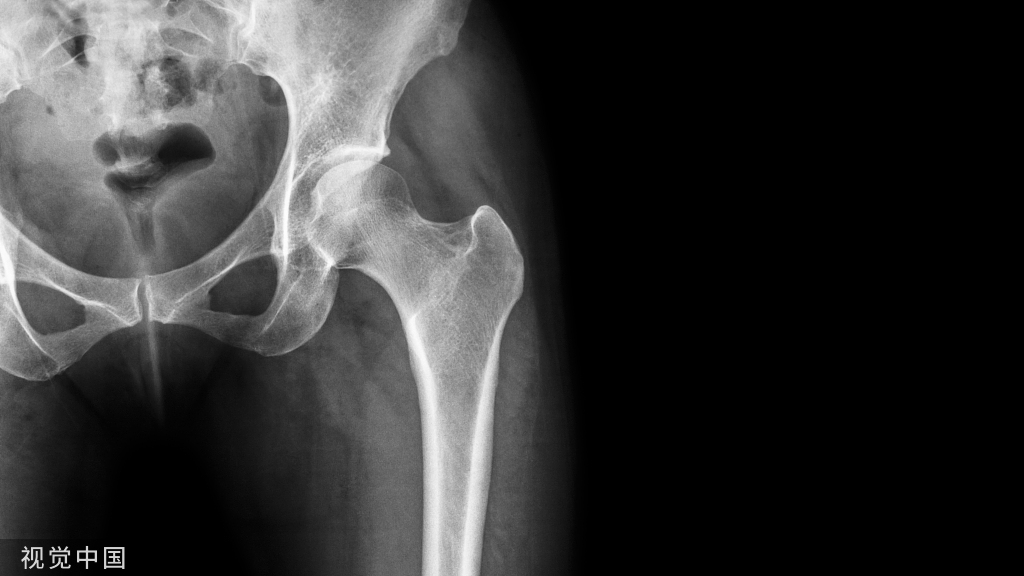

1.半髋关节置换